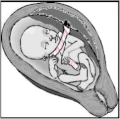

| Baby in the uterus with umbilical cord wrapped around its neck and arm | |

A nuchal cord is a condition in which the umbilical cord becomes wrapped around the fetus's neck.[1] Symptoms present in the baby shortly after birth from a prior nuchal cord may include duskiness of face, facial petechia, and bleeding in the whites of the eye.[1] Complications can include meconium, respiratory distress, anemia, and stillbirth.[1] Multiple wraps are associated with greater risk.[3]